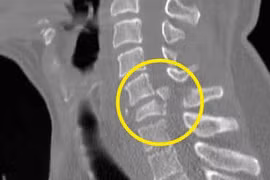

(khoahocdoisong.vn) - Đa phần bệnh nhân bị gãy trật cột sống cổ sẽ bị liệt hoặc tử vong. May mắn một bệnh nhân nữ 70 tuổi đã được phẫu thuật cứu sống không để lại di chứng sau 5 ngày bị gãy trật đốt sống cổ C4-C5 độ III.